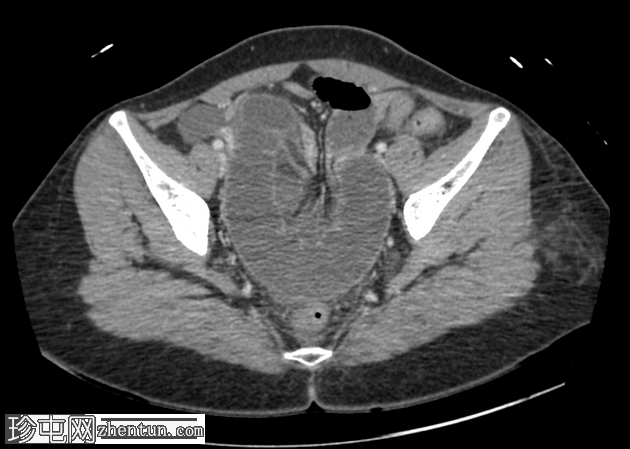

轴位增强扫描(门静脉期)

小肠袢明显扩张,左侧附件区可见双移行点,远端回肠短段闭袢梗阻,肠颈位于左侧输卵管/左侧子宫血管附近。

肠系膜血管充血,腹盆腔可见游离液体,提示肠系膜充血。

远端回肠袢和结肠已减压。

无肠缺血或穿孔的影像学证据。

CT 检查结果提示左侧附件水平小肠短段闭袢性梗阻。肠段的移行点和形态提示可能存在阔韧带或与左侧附件结构相关的粘连带引起的内疝。

剖腹探查发现一段小肠经左侧子宫阔韧带的小缺损处疝出并发生绞窄。复位绞窄的肠段后,缝合阔韧带缺损。